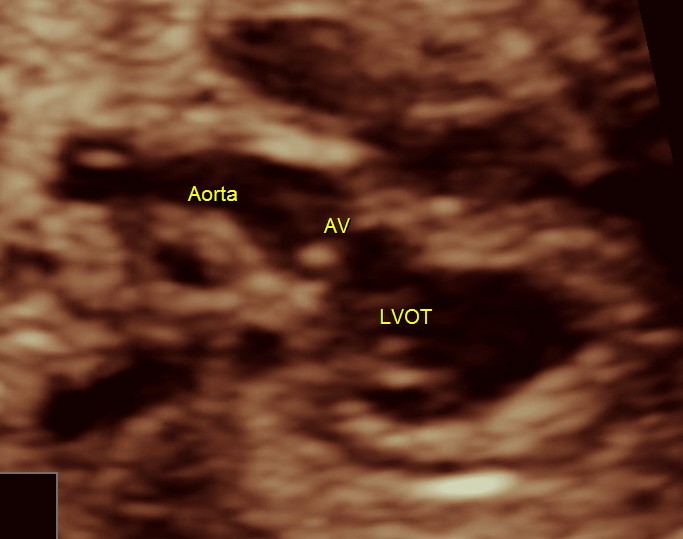

next is the normal outflow tracts and the normal 3 vessel view and the normal arches.

here we can see the pulmonary artery with its two branches arising from the lower (left) ventricle .and the aorta arising from the anterior (right ) ventricle.

vsd is seen in the picture below.